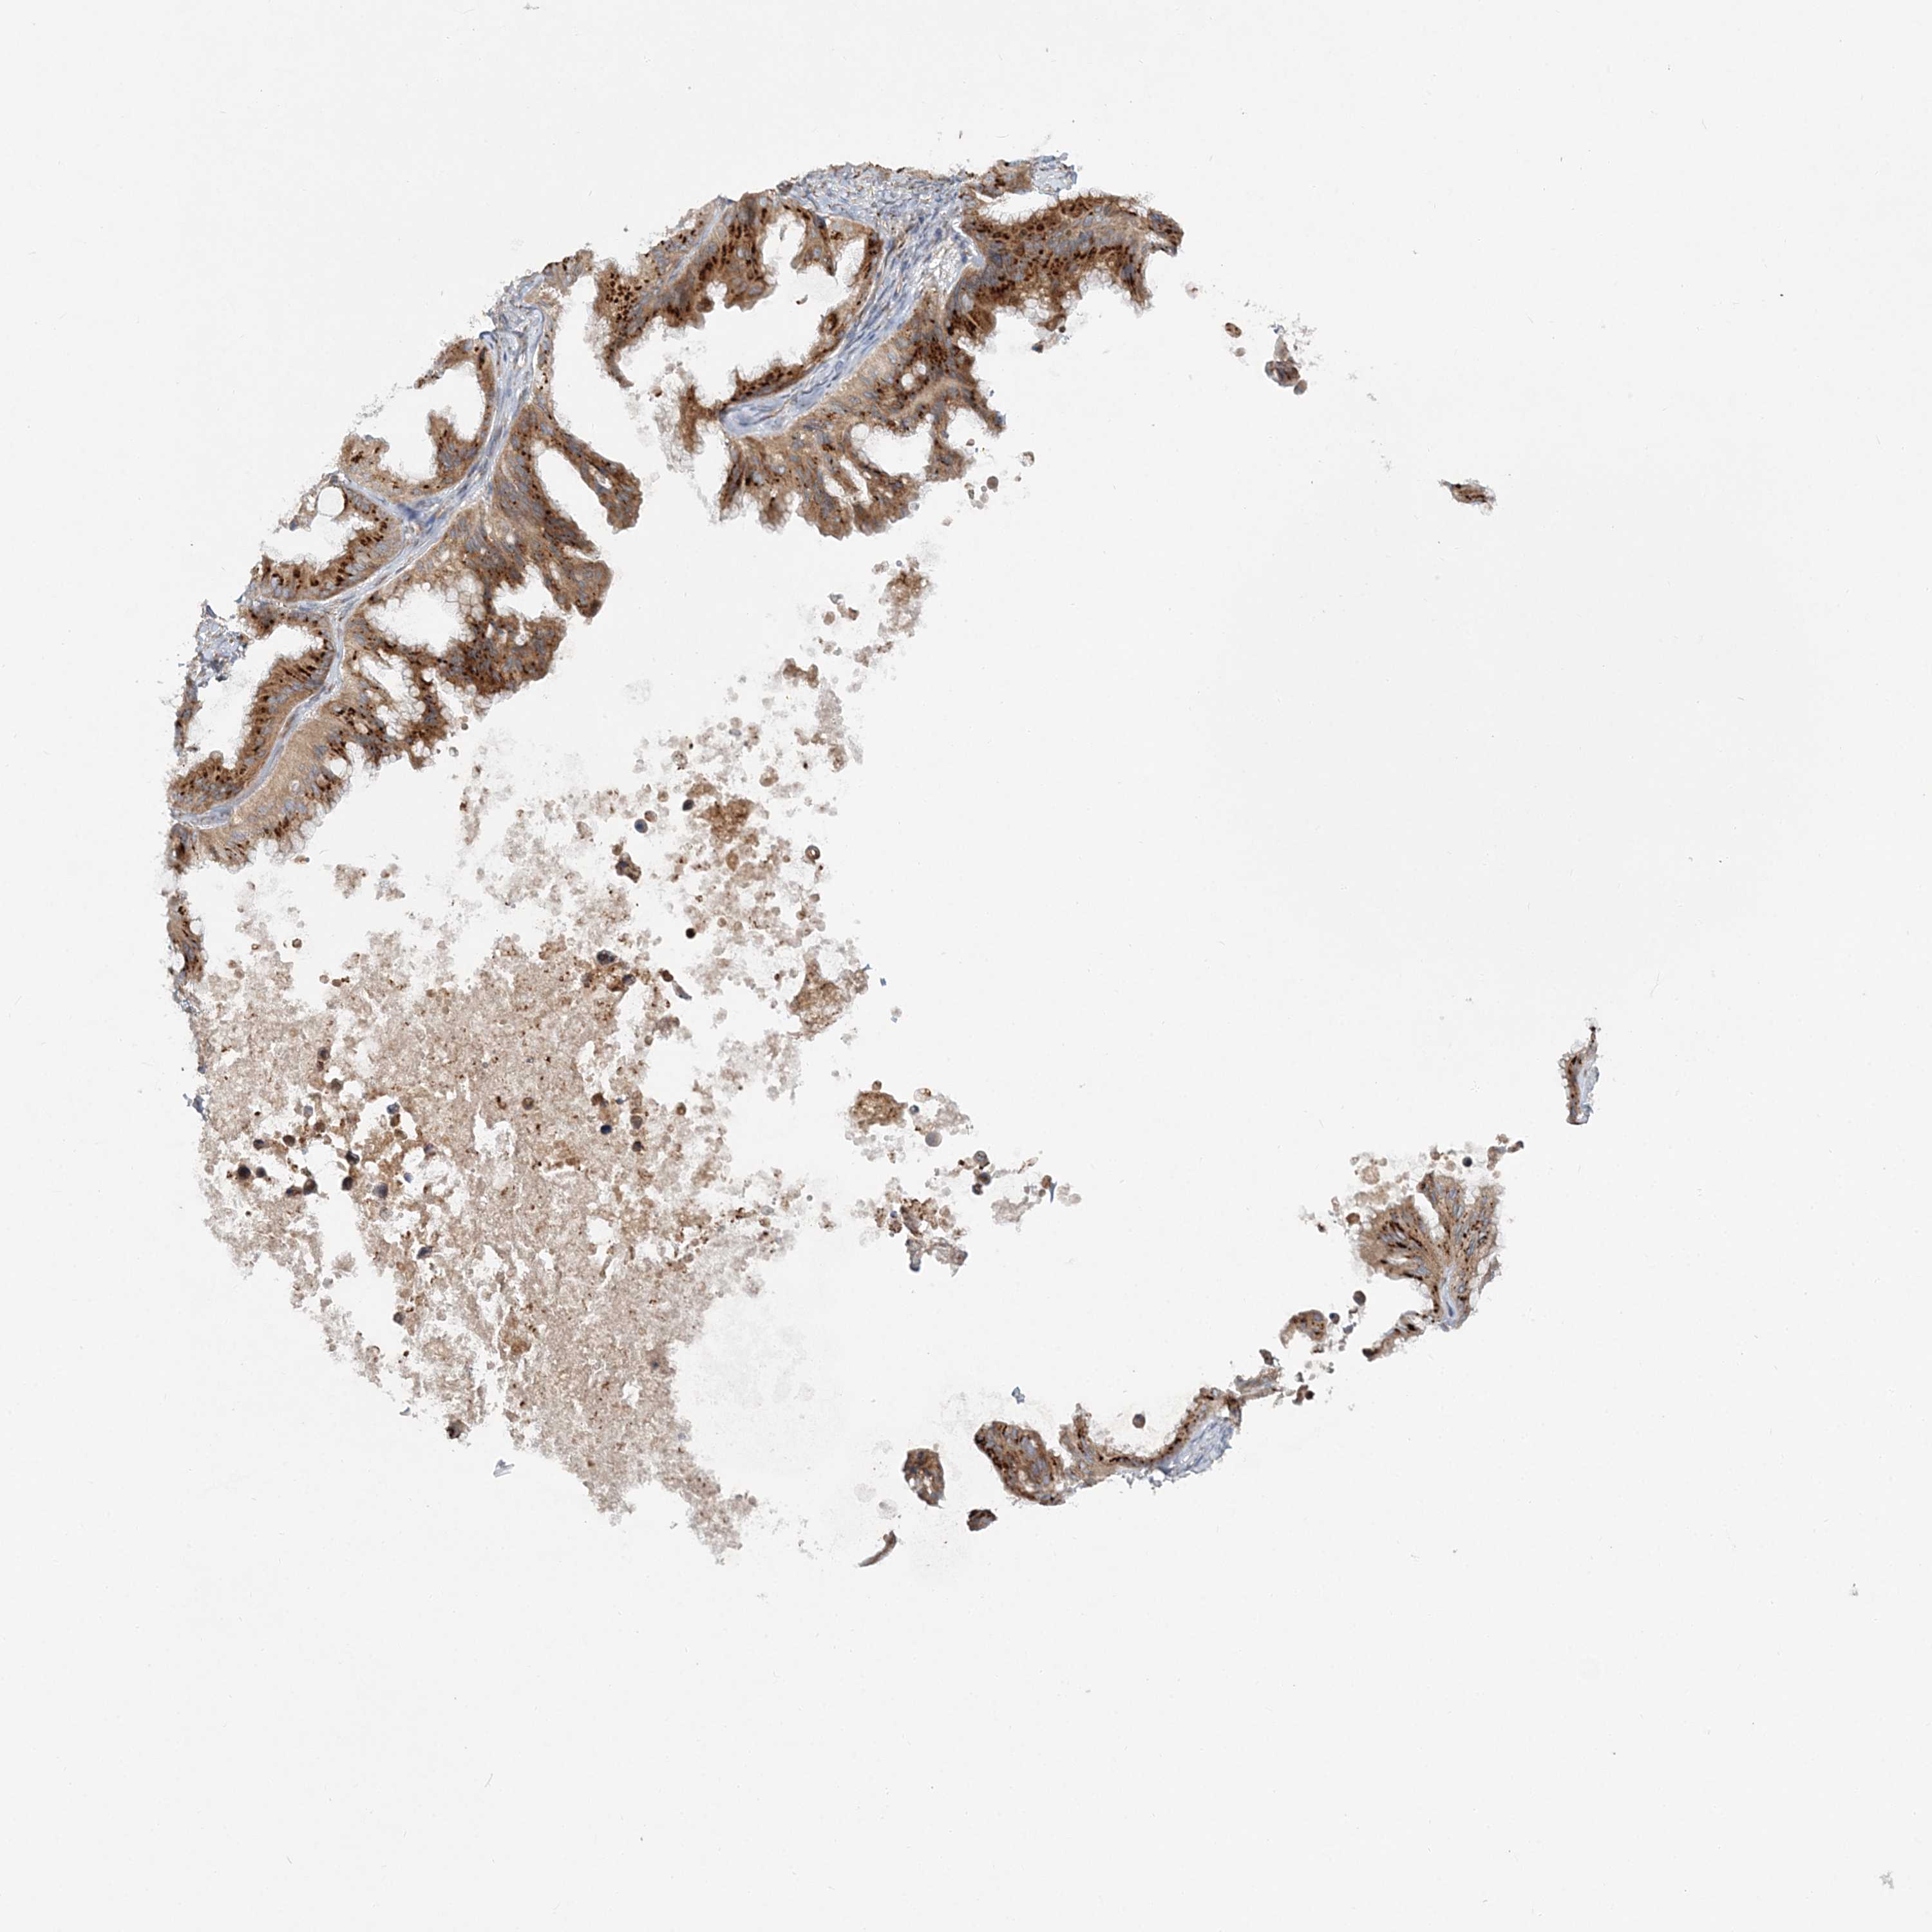

OVARIAN CANCER - Protein expressioni

A mouse-over function shows sample information and annotation data. Click on an image to view it in a full screen mode. Samples can be filtered based on level of antibody staining by selecting one or several of the following categories: high, medium, low and not detected. The assay and annotation is described here.

Note that samples used for immunohistochemistry by the Human Protein Atlas do not correspond to samples in the TCGA dataset.

Antibody stainingi

Antibody staining in the annotated cell types in the current human tissue is reported as not detected, low, medium, or high, based on conventional immunohistochemistry profiling in selected tissues. This score is based on the combination of the staining intensity and fraction of stained cells.

Each image is clickable and will lead to virtual microscopy that enables deeper exploration of all samples and also displays staining intensity scores, fraction scores and subcellular localization as well as patient and tissue information for each sample.

Antibody HPA036817

Staining

High

Medium

Low

Not detected

Intensity

Strong

Moderate

Weak

Negative

Quantity

>75%

75%-25%

<25%

None

Location

Nuclear

Cytoplasmic/membranous

Cytoplasmic/membranous,nuclear

Cystadenocarcinoma, serous, NOS

Carcinoma, endometroid

Cystadenocarcinoma, mucinous, NOS

Carcinoma, NOS